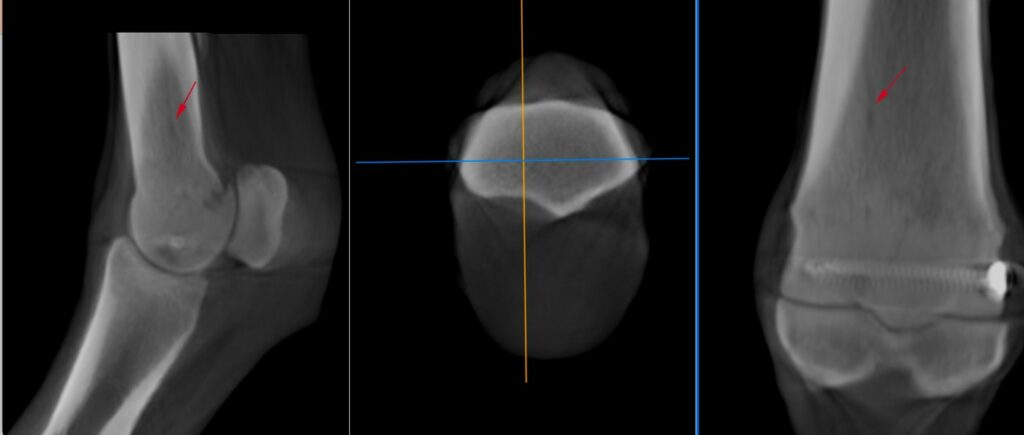

The area of osteolysis at the parasagittal groove of the medial condyle was well visualised, showing direct communication with the fetlock joint though two tracts (Figure 3). Additionally, the CT revealed a hypoattenuating line visible on all planes within the distal diaphysis of the third metacarpus extending from the region of the medial parasagittal groove spiralling medially, likely indicating a hair line fracture (Figure 4).

Despite the artefacts caused by the metal screw, assessing for fetlock fracture with a CT scan allowed for an efficient and detailed evaluation, something that would have been impossible with MRI due to metal artefact. The initial suspicion of a fetlock fracture was dispelled however, revealing that the observed structures were blood vessels. However, the CT scan identified a second area of potential fracture. As a result, ongoing monitoring and a follow-up CT scan in a few weeks were recommended.